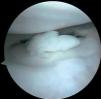

Figura 7 Artroscopia. Cuerpos libres alrededor del ligamento cruzado íntegro.

Figura 8 Artroscopia. Cuerpos libres alrededor del ligamento cruzado íntegro.

Se practica artroscopia, en la que se observan (figs. 2, 4, 6-8):

• Múltiples fragmentos condrales libres de bordes agudos, que se identifican como recientes y de bordes redondeados que se catalogan como antiguos.